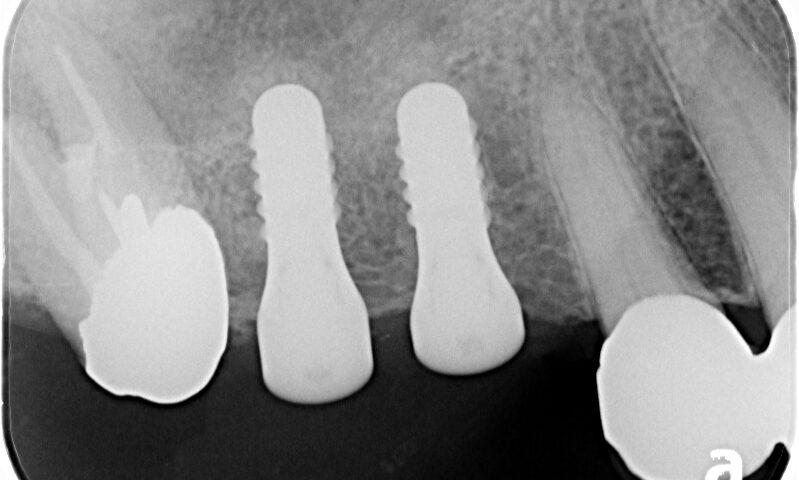

インプラント症例その8

インプラント症例その7